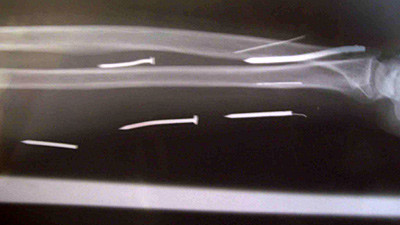

Dar durerile au dat-o de gol fiind dusa la un control medical de catre familie. Abia atunci, medicii i-au descoperit cele 24 de cuie raspandite in tot corpul. Femeia a fost supusa unei interventii pentru a scapa de cuie. Spre norocul acesteia, niciun organ nu i-a fost afectat.